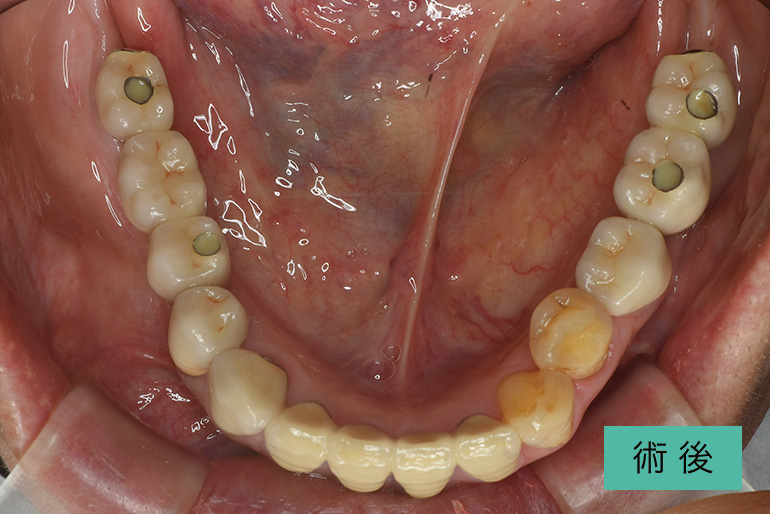

上顎総インプラント

| 治療内容 | 両側サイナスリフト(上顎洞底挙上骨造成術)し、上顎総インプラント治療を行った |

|---|---|

| 治療期間・回数 | 1年9ヶ月、29回(他部位の治療を含む) |

| 費用(税込) | ¥4,935,000 ※自由診療 |

| リスク・副作用 | 疼痛、腫脹、出血、鼻血、青痣、補綴の脱落、インプラント周囲炎、神経麻痺 |